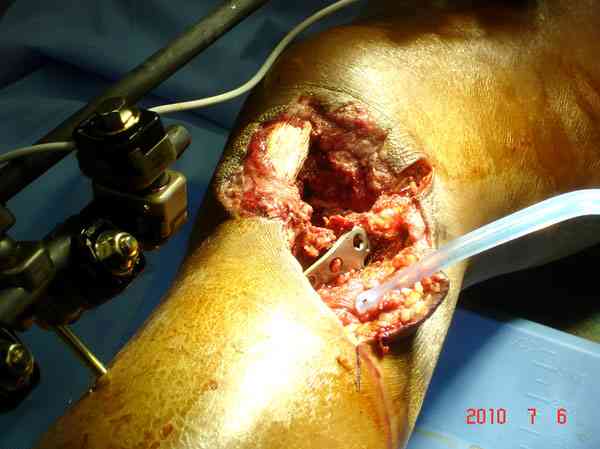

Поступила к нам пациентка 19 лет с диагнозом "Состояние после открытого многооскольчатого перелома дистального метаэпифиза правого бедра, проксимального метаэпифиза большеберцовой кости". Травма в июне 2010 года в Индии. ДТП.

Тамошние доктора выполнили ПХО с удалением фрагментов латерального мыщелка бедра. Наложен АВФ. По возвращению в Украину через 1,5 месяца АВФ демонтирован. И так как смещение фрагментов бедра не устранено, было принято решение после заживление ран от стержней выполнить МОС. Не сколько для четкой анатомической репозиции сколько для подготовки к установке эндопротеза в будущем. Что и было выполнено 10 августа. Интраоперационная картина следующая. Дефицит практически всего латерального мыщелка бедра. Была выполнена попытка закрепить то что осталось от мыщелка, но он развалился на фрагменты. ВЫполнен ситуационный синтез спицами. Дефект заполнили бикортикальным трансплантатом из крыла подвздошной кости, МОС страйкеровским фиксатором. В послеоперационном периоде к 10 дню начались боли, гипертермия. Повышение СОЭ, лейкоцитоз. Посев крови транзиторная бактериемия золотистого стаф. Взяли в операционную. Выполнили дренирование сустава и области п\о раны. Получили гематому фактически с гноем. Температура нормализовалась. Назначили ванкомицин по 1000 мг 2 раза в день.который принимает с 28 августа по сей день. Температура нормальная, СОЭ на убыль. Посевы отделяемого стафилококк 2 ст активности. Но отделяемое по дренажам продолжает идти в достаточном количестве. Взял посев, сеется стаф. 3 ст активноси. К ванкомицину, понятно, слабочувствителен. Что в этой ситуации посоветуете?

Коллеги фиксатор Numelock II

Здесь применение материала Plexur http://www.plexur.com для пластики при дефектах кости у больной с огнестрельной раной латерального тибиал плато с повреждением малоберцового нерва. Несмотря на интактный медиальный мышелок, для профилактики от вальгуса установлен АВФ и сделана ангиограмма.

После нескольких обработок и вакуумирования, поэтапно сделана фиксация тибиального бугра шурупами. И окончательную фиксацию закончили латеральной пластиной для тибиал плато и установкой пластического материала.

Для закрытия мягкотканых дефектов привлечена другая служба.